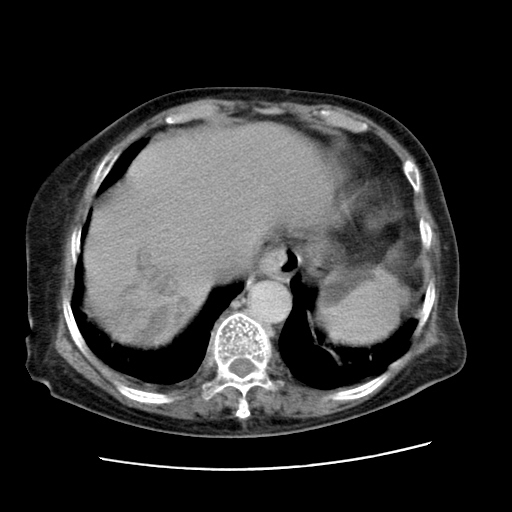

女,77.无不适

肝脏变异、异位胆囊,肝右叶肝内胆管结石并肝内胆管扩张。

肝脏变异

肝右叶肝内胆管结石并肝内胆管扩张

胆总管扩张

肝右叶肝内胆管结石并肝内胆管扩张。胆总管下段梗阻,考虑壶腹部占位。